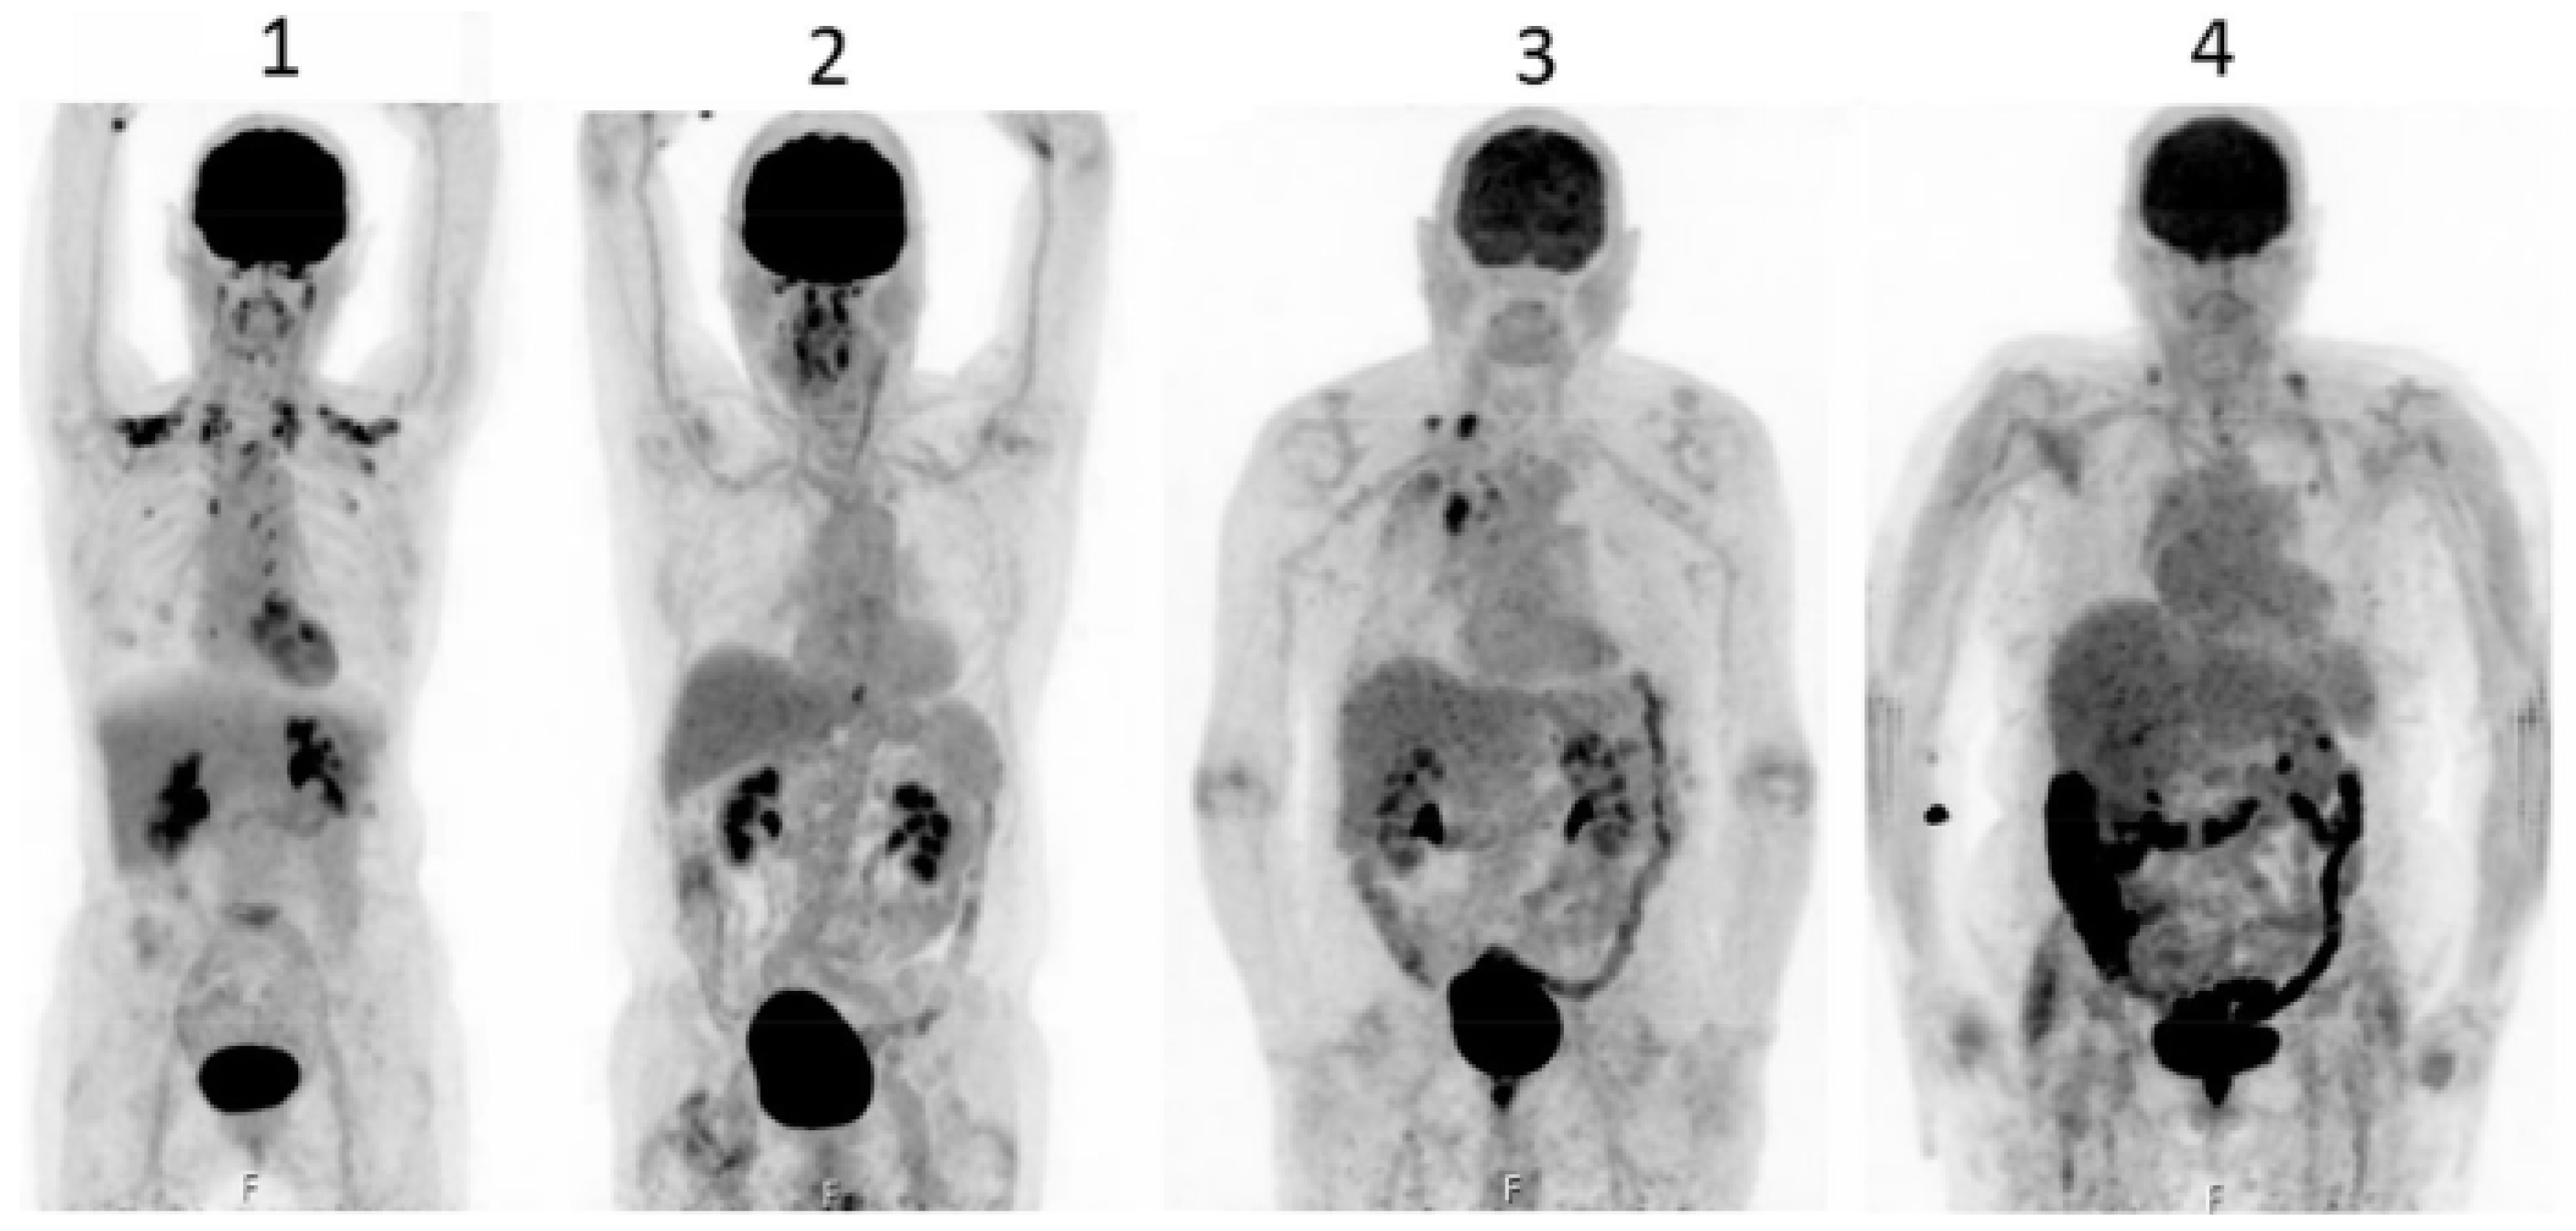

C11-metformin (9.5 microSv/MBq=ca.1.1 microgram), first injected intravenously, allowed to study its biodistribution in humans (70) by the PET-scan technique.Most of the activity was found in the liver,the kidney and the urinary bladder.Activity peaked immediately after injection and most of the compound was cleared from the blood 20 minutes after injection.In the kidney there was a quick intense activity (80% of the injected activity) with an equally rapid decrease with a reversibility velocity similar to that of the liver but faster.In the liver the peak of the activity was of course lower (15% of that in the kidney) because of the much larger volume of the cellular distribution (Fig 1 upper panel).

After rapid ingestion of the strong basic compound C11-metformin (18.1micro Sv/MBq,half-life= 20.4 minutes) dissolved in water containing 100mM (NH4)2-HPO4 [pH=5], consecutive whole-body scans were performed.Dosimetry calculations were performed for the stomach content,small intestine,liver, kidney and bladder content.It was demonstrated that hepatic metformin uptake is very rapid and fully reversible but the accumulation of the activity is higher than after the intravenous administration, as ,although slower, the tracer delivery comes from the portal blood through the liver first.Two hours after the oral ingestion of the tracer the bulk of the radioactivity is still in the intestine (Fig.1 lower panel) and no further observation of the fate of the radioactive metfomin was possible.

Figure 1. Scans of C11-metformin administered to humans intravenously and orally (lower and lower panel respectively) taken at different time after administartion .Gormensen LC et al.(70,with permission).